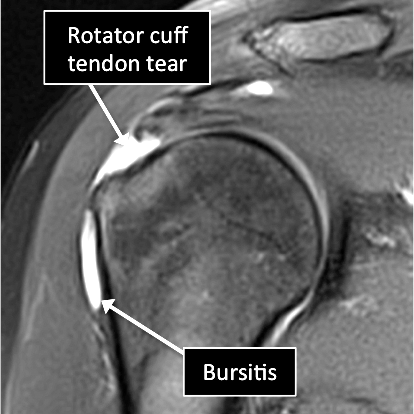

MRI examinations showing normal shoulder (top) and a rotator cuff tear and bursitis (bottom).

- MRI allows us to see many of the different structures in the shoulder.

- Several injuries or diseases affecting those structures can be diagnosed using MRI.

- Common things include labral tears or degeneration, damage to the joint capsule, tendons or ligaments that contribute to shoulder stabilization, osteoarthritis, tumors, among others.